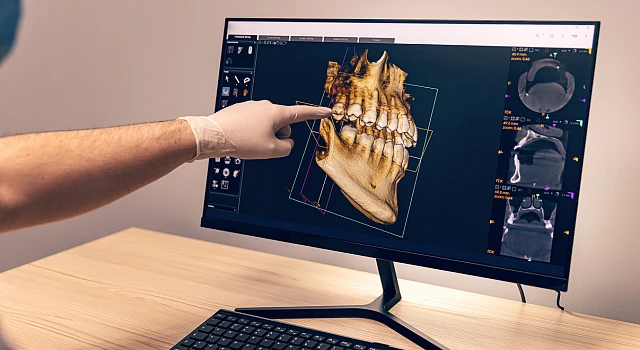

Цифровая диагностика и визуализация

Цифровая диагностика и визуализация

Полное обследование полости рта

Снятие оттиска

Определение прикуса

Визуализация цифровой модели челюсти

Индивидуальный подход и планирование — основа безошибочной имплантации

Мы не устанавливаем импланты «на глаз»

Перед имплантацией «Все на 4» в клинике «Один к Одному» проводится расширенная 3D-диагностика по 65 параметрам

Хирургический шаблон исключает ошибки и позволяет ввести каждый имплант строго в заданную позицию, сохранив костную ткань и снизив травматичность процедуры. Это особенно важно при полной реконструкции зубов.

3D — моделирование будущей улыбки

3D — моделирование будущей улыбки

Создание виртуальной модели будущей улыбки с учетом показателей диагностики, которое позволяет пациенту увидеть и даже «примерить» новые зубы еще до начала лечения

Планирование положения имплантов

Планирование положения имплантов

Моделирование расположения имплантов для их оптимального положения относительно соседних зубов, нервов и мягких тканей

Создание хирургического шаблона и протокола имплантации

Создание хирургического шаблона и протокола имплантации

Планирование глубины, диаметра и оси введения импланта для гарантии высочайшей точности операции. Установка имплантов в единственно правильной позиции с помощью хирургического шаблона

Имплантация без операции стала реальной с помощью хирургического шаблона. В этом случае хирургу не нужно разрезать десну – достаточно сделать прокол диаметром несколько миллиметров